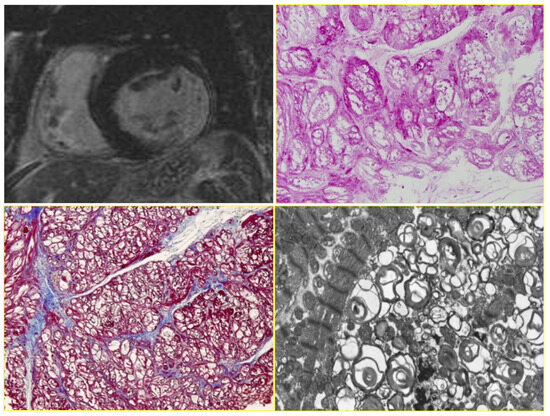

7. Clinical Indications of Endomyocardial Biopsy

9. Diagnosis of ACM Through Endomyocardial Biopsy and Infiltrative Disease as Amyloidosis

- Perazzolo Marra, M.; Thiene, G.; Rizzo, S.; De Lazzari, M.; Carturan, E.; Tona, F.; Caforio, A.L.; Cacciavillani, L.; Marcolongo, R.; Tarantini, G.; et al. Cardiac Magnetic Resonance Features of Biopsy-Proven Endomyocardial Diseases. JACC Cardiovasc. Imaging 2014, 7, 309–312. [Google Scholar] [CrossRef]